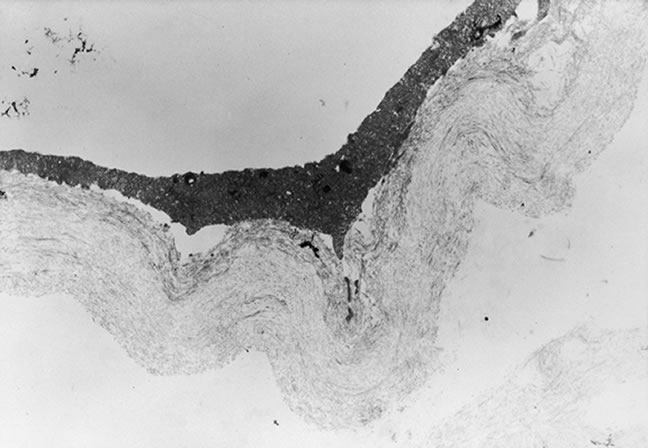

The anterior vitreous cortex or anterior hyaloid is the anterior surface layer or condensation of the vitreous body. There is no specialized membrane that constitutes the anterior vitreous cortex, but instead there is a greater density of collagen fibrils. Microscopically, the framework of collagen fibrils that run throughout the vitreous body ends in an interwoven network to form the anterior vitreous cortex. The superficial fibrils tend to run parallel to the surface in this region. The smooth surface and membrane-like appearance are due to the lamellar distribution of the cortical fibers and the associated highly polymerized mucoproteins.4,5 Anatomically, the anterior hyaloid forms the posterior limits of the posterior chamber. This portion of the vitreous cortex functions in the physiologic communication between the vitreous cavity and the aqueous humor. The anterior surface of the vitreous body separates from the pars plana approximately 1.5 mm anterior to the ora serrata. It extends medially to contact the lens posterior to the lens equator. Thus, the anterior hyaloid is in contact with the ciliary processes and the lens zonules, as well as the posterior lens capsule. The vitreous attaches to the lens capsule in a ring-like manner, forming the hyaloideocapsular ligament of Wieger. This ligament is believed by some to be synonymous with the attachment ring of the posterior zonular fibers.4 The circular area of attachment measures approximately 9 mm in diameter and is especially firm in younger persons or after intraocular inflammation.5 In this circular area the anterior hyaloid is thickened. Central to the attachment of Wieger's ligament (also known as Egger's line), the vitreous lens attachment is less pronounced and appears to be due to surface tension. This central area contains a potential space within the 9-mm ring known as Berger's space, or the patellar fossa. The anterior hyaloid then turns posteriorly to form the anterior portion of Cloquet's canal in the midportion of Berger's space. Cloquet's canal represents the remnants of the primary vitreous and can sometimes be seen with the slit lamp. It arises from the optic disc in a funnel-shaped manner, in the area of Martegiani, and extends forward to the posterior lens surface. The canal is 1 to 2 mm in width and has a down turn in the central vitreous cavity. The area of contact with the posterior lens capsule can at times be identified by a tag of embryonic tissue, known as a Mittendorf dot, located slightly nasal to the posterior pole of the lens. Similarly, a remnant of the posterior primary vitreous can occasionally be identified on the optic disc. This remnant, representing the embryonic point of exit of the hyaloid vascular system from the optic nerve head, is known as Bergmeister's papilla. The walls of Cloquet's canal are formed by a vitreous condensation rather than a true membrane (see Fig. 1).

The mechanical relationship between the vitreous and the retina is mediated by the posterior vitreous cortex, which is also called the posterior hyaloid. The posterior vitreous cortex consists of relatively densely packed type II collagen fibrils arranged tangentially to the retina. The retinal basal lamina is the basement membrane of the Müller's cells that comprise the internal limiting membrane (ILM) of the retina.6,7 Ultrastructurally, the ILM consists of three layers.8 Adjacent to the end feet of the Müller's cells is the lamina rara interna. The lamina rara externa is contiguous with the vitreous cortex. In between these layers is the lamina densa. Collagen fibers of cortical vitreous are tangential to the lamina rara externa. The ILM is composed of primarily type IV collagen but also contains fibronectin, laminin, and type I collagen.9 The morphology of the ILM varies topographically in the retina. The ILM, and in particular the lamina densa, is thin in the retinal periphery and becomes increasingly thicker and irregular in the posterior retina.6,8

The nature of the adhesion between the vitreous cortex and the ILM is enigmatic. This adhesion is strongest at the optic nerve, the macula, the vitreous base, and retinal vessels. Foos6 demonstrated attachment plaques between Müller's cell cytoplasm and the ILM in the basal and equatorial retina (Fig. 2). Vitreous traction mediated by vitreous fibrils may contribute to these adhesions. These attachment plaques are not present posterior to the equator except where the ILM is thinned in the fovea. This anatomic variation in the fovea region may play a role in the pathogenesis of some of the vitreomacular disorders.